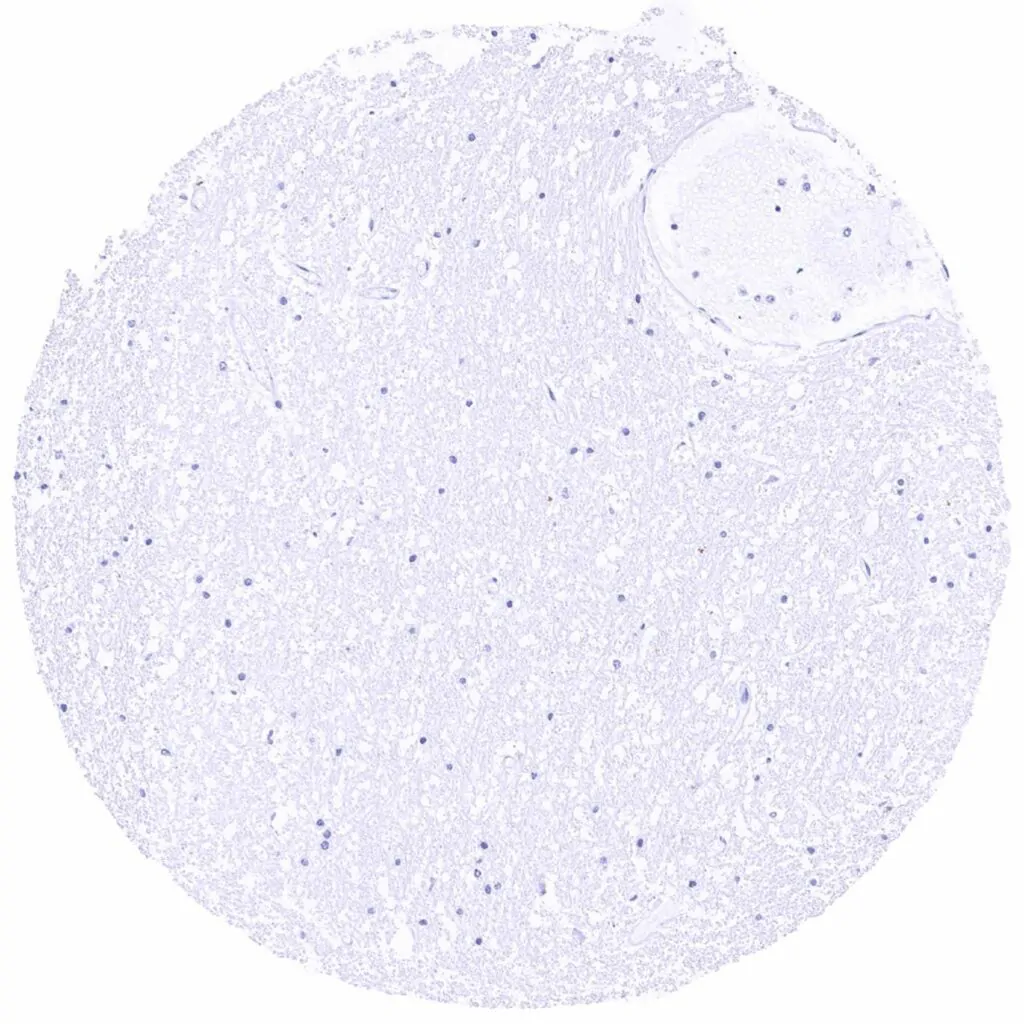

Cerebellum (white matter)

Cerebellum, cortex (molecular layer, Purkinje cell layer, granule cell layer)

Cerebrum, grey matter